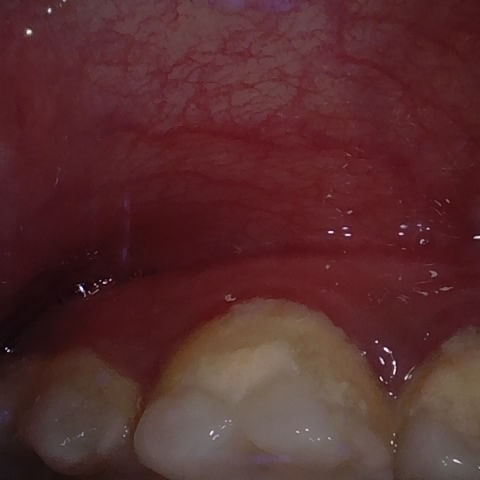

Annotated as "Good"